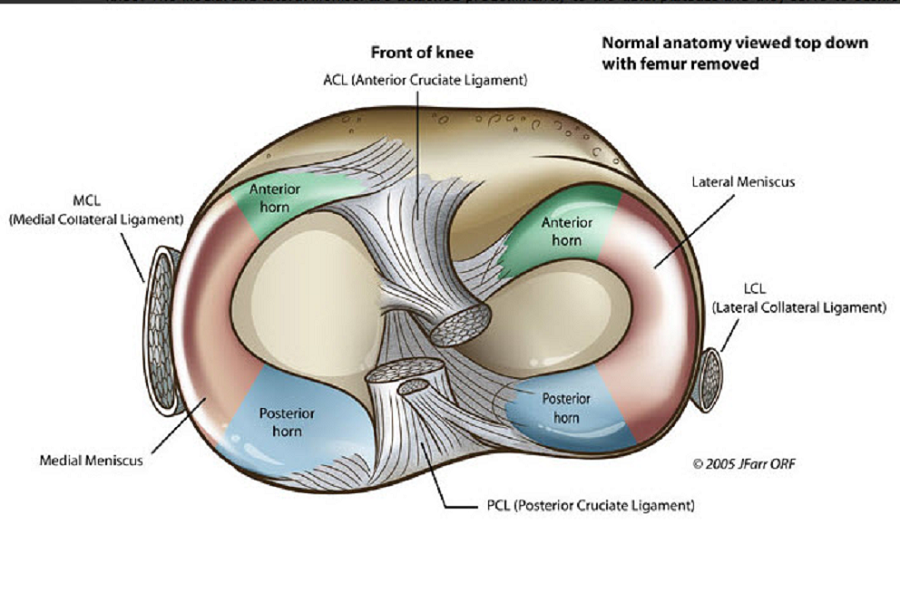

Анатомические изображения менисков и коленного сустава